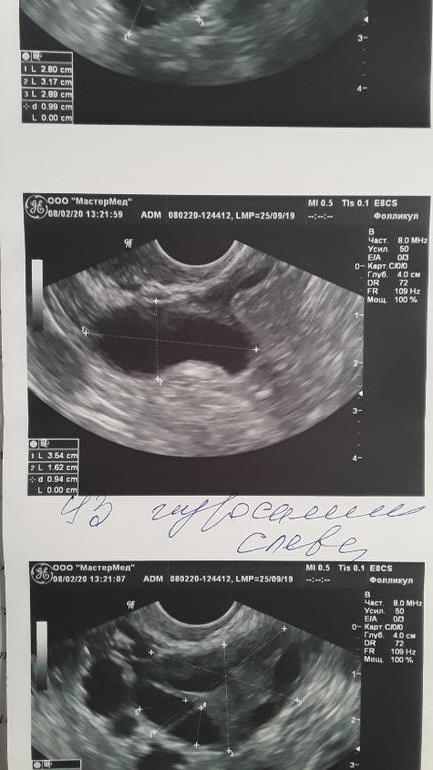

Лапароскопия, гистероскопияЗдравствуйте,не знаю,что делать!! Делала узи на 14 д.ц,там узистка увидела у меня гидросальпинкс с лево😢 и говорит,что надо удалять трубу! Она у меня одна осталась правда не проходимая,но все же,лишиться последний трубы хоть и не рабочей для меня морально тяжело!!На 18 день цикла я поехала к своему РЕ ,рассказала ей,что обнаружили гидросальпинкс(( Она сделала мне УЗИ сама и говорит,что это сосуд.и гидросальпинкса у меня нет!! Что делать и кому верить не понятно! Девчонки Вы что думаете по этому поводу??Узистку которая делала узи на 14 д.ц,хвалят,но и Ре тоже вроде хороший специалист. Девочки модераторы не могу в какую категорию отнести свой пост,извините пожалуйста!1

Я с гидросом много лет жила. Судя по узи, я согласна, что это гидрос, причем многокамерный. Обычно, что бы на узи точно подтвердить, его немного "колыхают" и видно жидкость, она переливается на экране. Я бы шла на диагностическую лапару. Если он, то удалять. Его лечить бесполезно, вернется опять. Поверьте, я жалею, что теряла время и берегла трубу( решиться тяжело, но время летит(

Многокамерный) да, если второе фото с гидросом, то скорее всего такой. Он перетекает из полости в полость между спайками